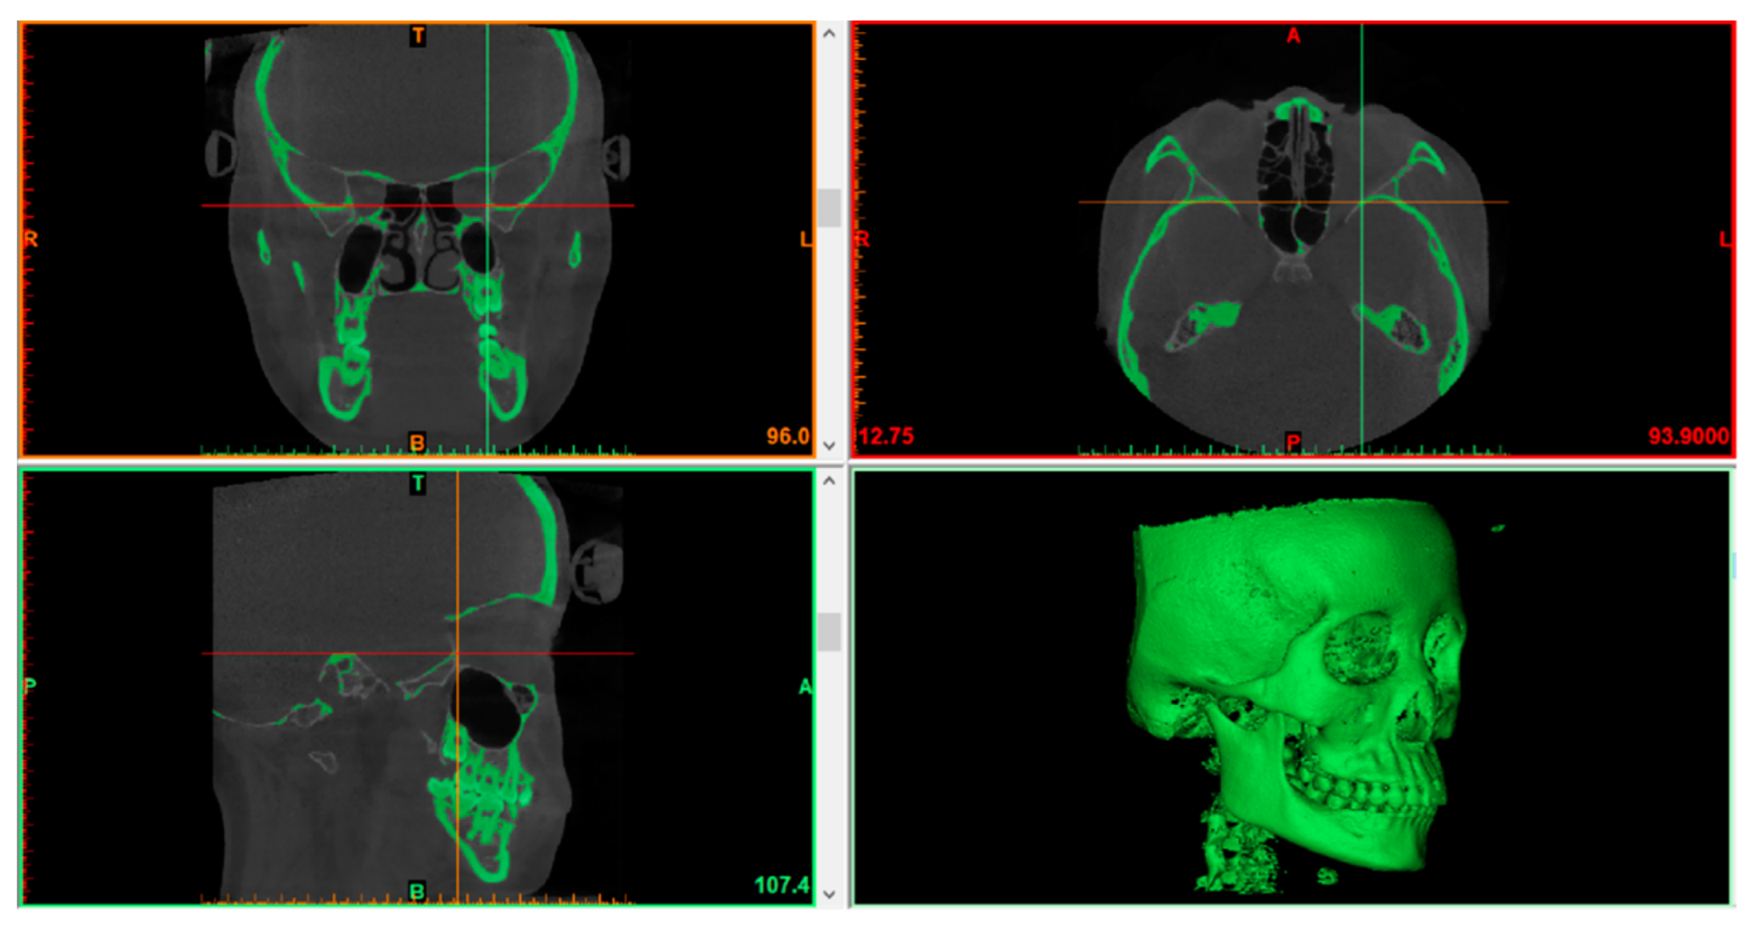

2.2.1. Segmenting Images

2.2.2. 3D Models Rendering and Mirroring